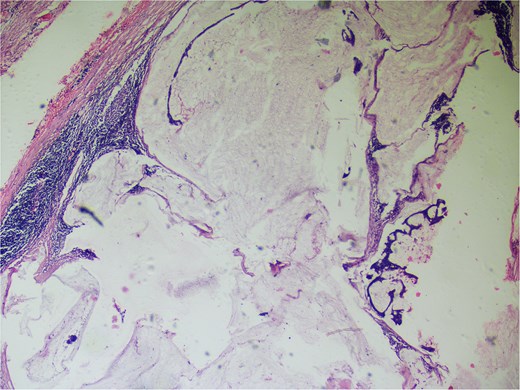

On gross examination, growth seen involving ileocecal junction extending upto caecum measuring 6.5 × 6.0 × 4.3 cm. Cut section showed solid creams white firm to friable areas with mucoid consistency at places. A nodular growth is identified in the attached mesentery measuring 3.5 × 2 × 2 cm. On cut section solid white areas are seen along with focal area showing mucoid consistency. The histopathological report concluded mucinous adenocarcinoma of caecum, pT3N1MX, with evidence of lymphovascular invasion. The tumor invaded through the muscular propria layer (Figs 4 and 5). Additionally, acute appendicitis was found.

Hematoxylin and eosin ×40: Section shows lymph node effacement of by pool of mucin and few atypical cells and the periphery show compressed lymphoid tissue.